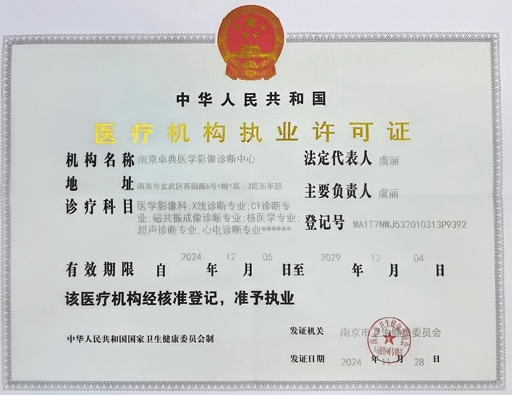

医疗资质认证

江苏省首家第三方独立医学影像诊断中心,具备完整的资质认证,确保服务的合法性和专业性

权威认证保障

所有证书均由相关政府部门和权威机构颁发,确保我们的服务符合国家法规要求,为合作伙伴提供可靠的质量保障。我们承诺持续更新和维护各项资质认证,确保服务的合规性和专业性。

合规资质

持有正规《医疗机构执业许可证》,所有医师均具备中级职称以上资质,合作医疗机构无需承担合规风险